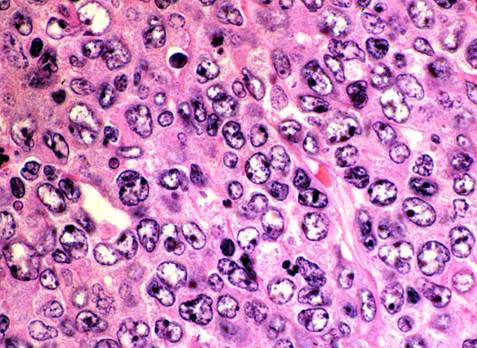

Hình ảnh giải phẫu bệnh: các tế bào u lớn, bào tương hẹp, nhân lớn có 2-4 hạt nhân, chất nhiễm sắc thô.

Hình ảnh nhuộm hóa mô miễn dịch dương tính với CD20.